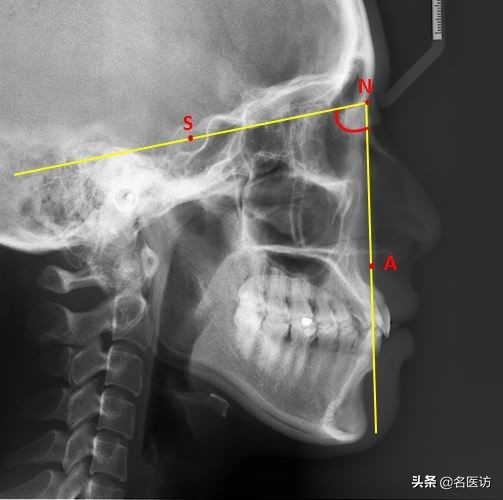

1、评估面型:SNA角

面型可粗略的分为3大类:直面型、凸面型、凹面型。其中,直面型是公认的最符合审美的面型,SNA角可以帮助我们了解自己的面型和凹凸度。

N:鼻根点,鼻额缝的最前点

S:蝶鞍点,蝶鞍影响的中心

A:上牙槽座点,鼻子和上牙槽接触的最凹点

当该角过大时上颌前突,面部侧貌呈凸面型;反之上颌后缩,面部呈凹面型。